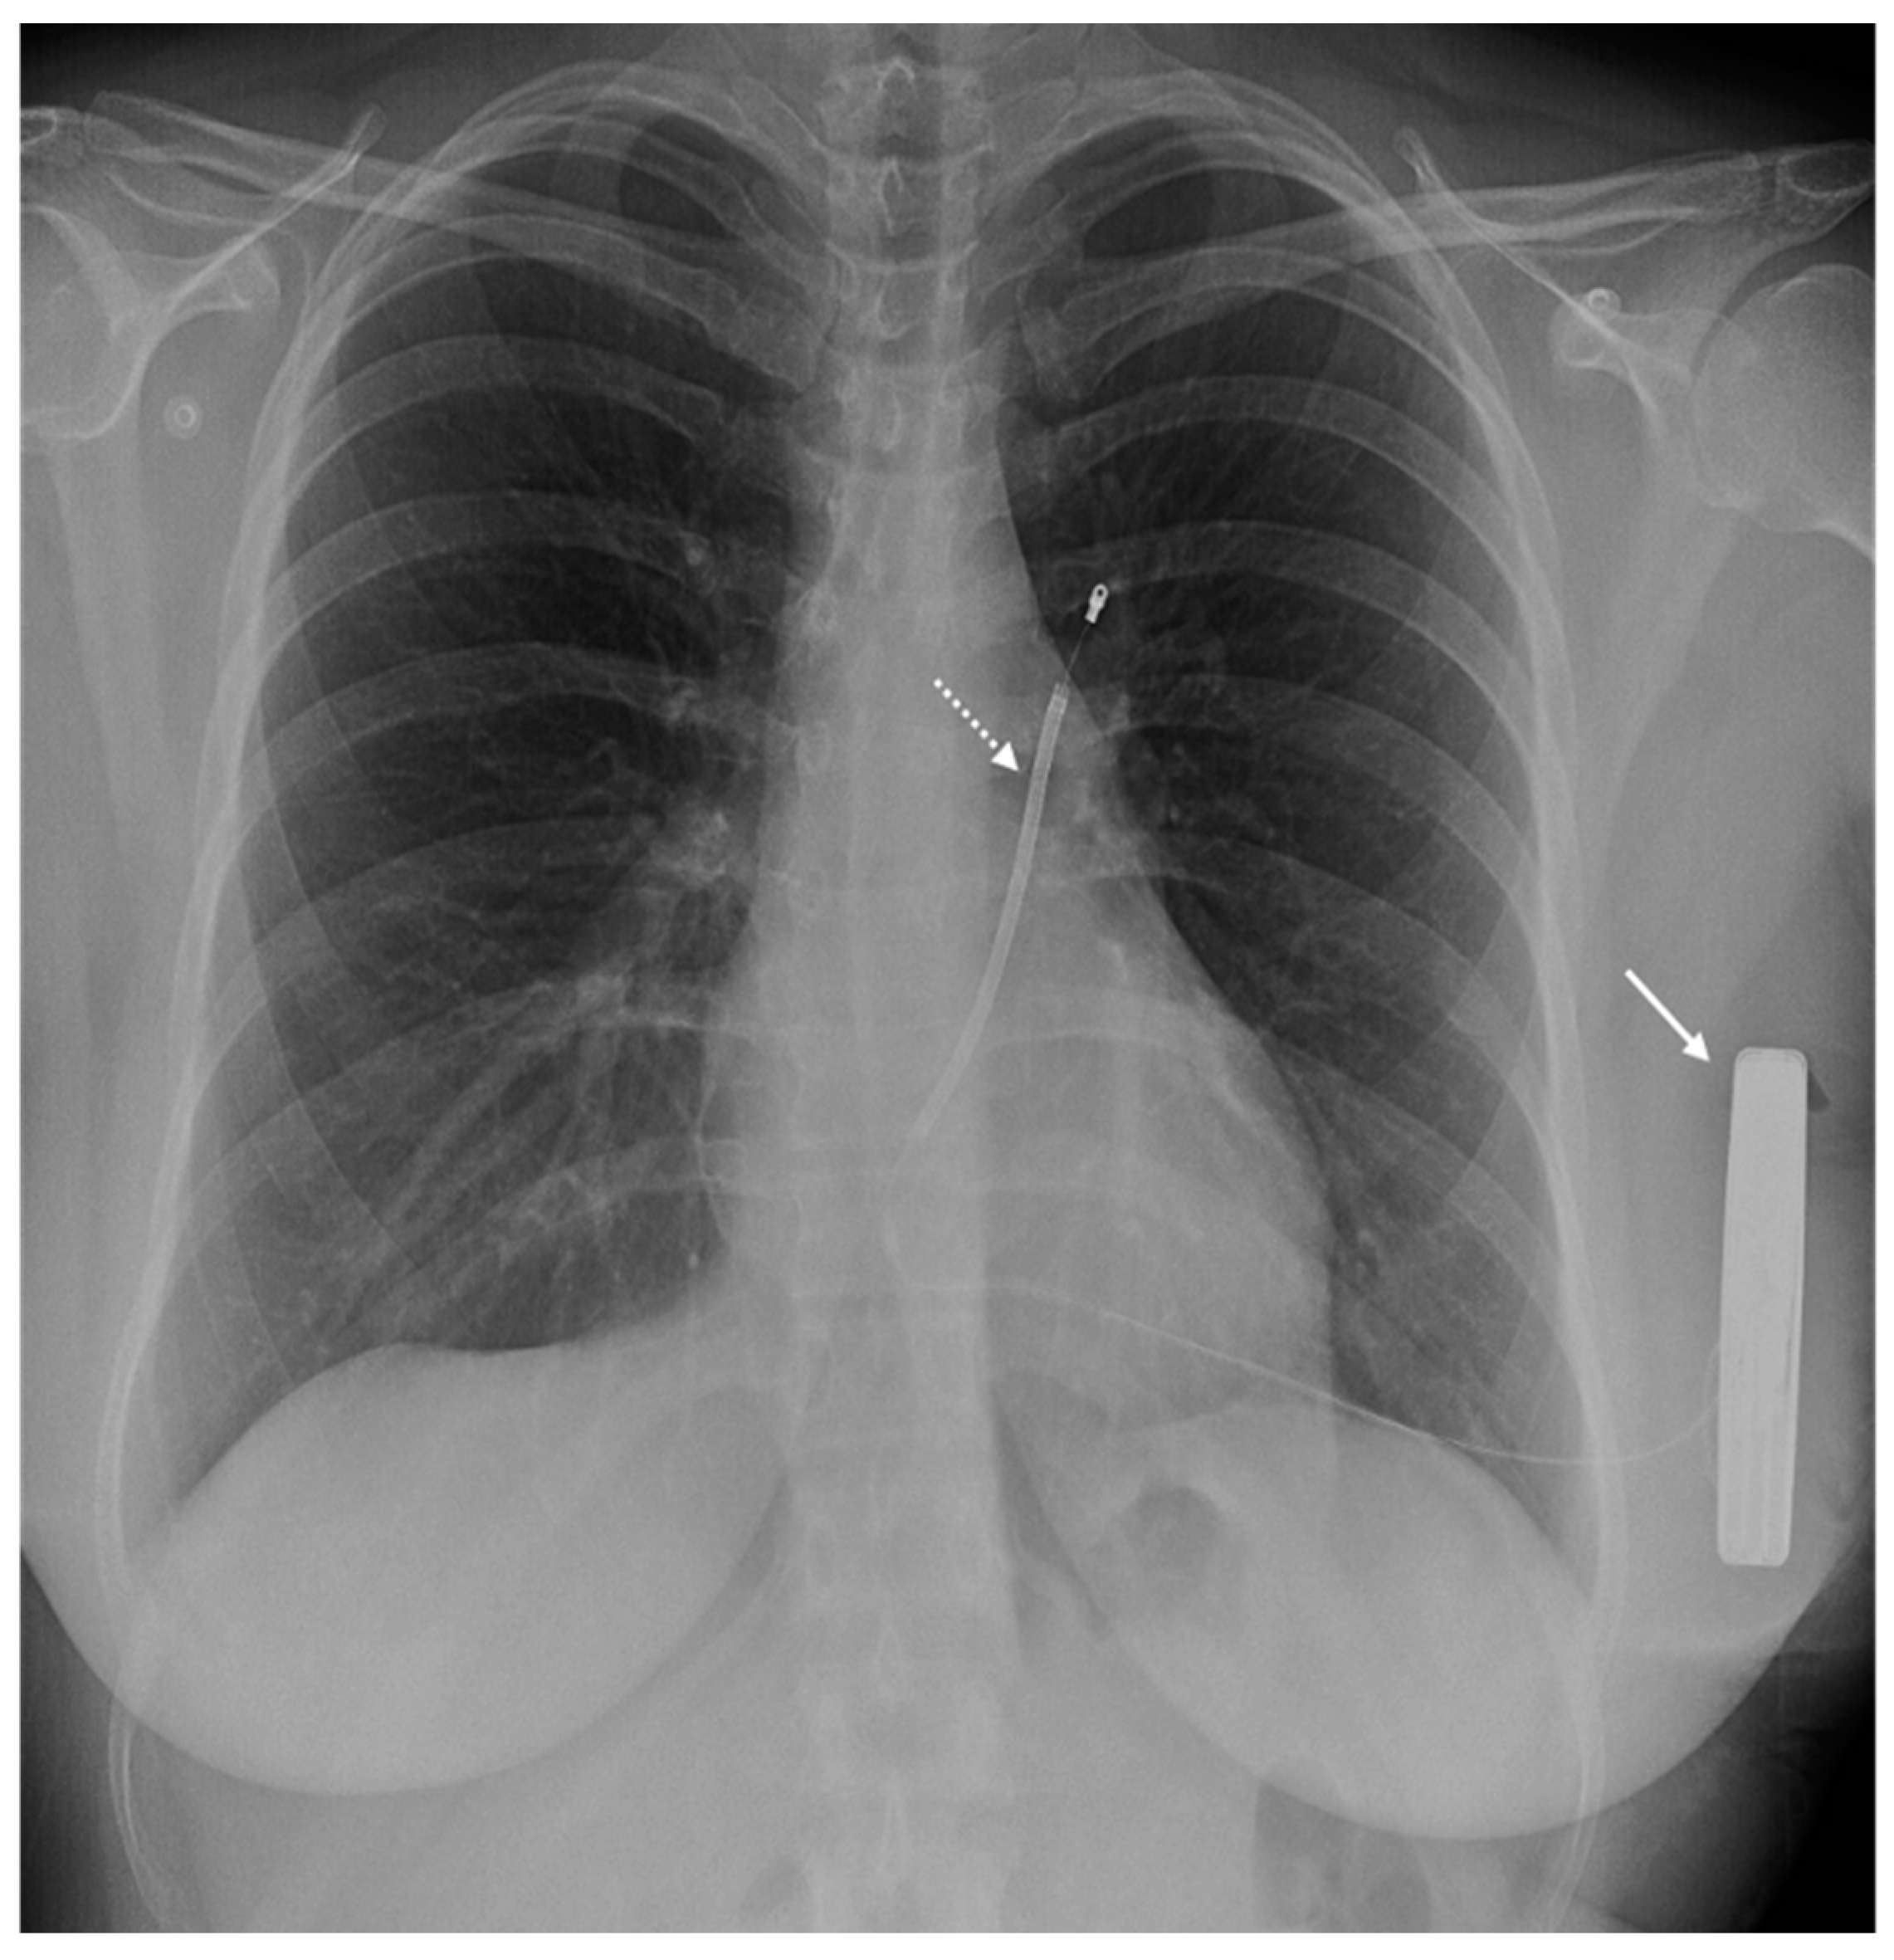

- Bučić, D.; Hrabak-Paar, M. Multimodality imaging in patients with implantable loop recorders: Tips and tricks. Hell. J. Cardiol. 2023, in press. [Google Scholar] [CrossRef]